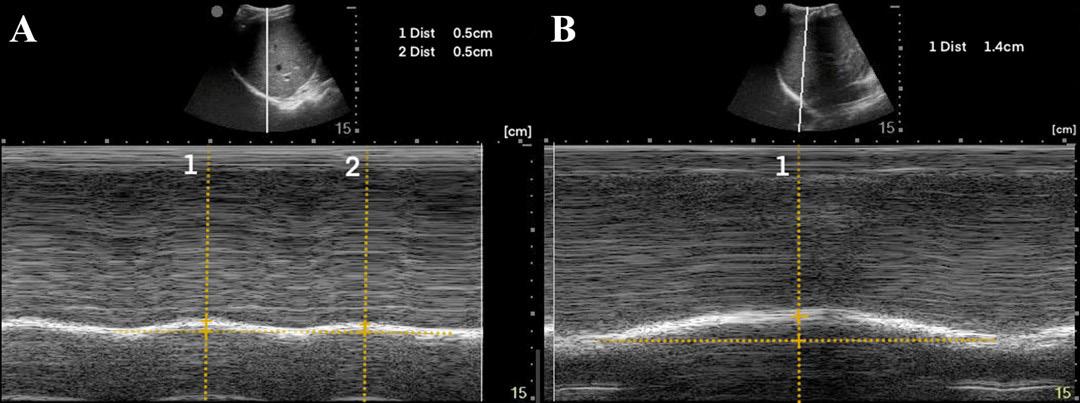

To measure diaphragmatic excursion the patient is first placed in a supine position. A curvilinear probe is placed in the midaxillary line and oriented cephalad to optimally visualize the inferior aspect of the lungs, diaphragm, and upper abdomen (ie, spleen or liver). Diaphragmatic excursion was quantified on M-mode imaging, with the M-mode cursor directed through the diaphragm. The amplitude of diaphragmatic excursion was measured from the baseline to the point of maximal excursion on the vertical axis (Image 1).

A 44-year-old man presented after a motorcycle collision and was found to have right-sided fractures of ribs 2-5 and 12 on computed tomography (CT). The patient continued to report severe pain after 100 micrograms (mcg) of intravenous (IV) fentanyl. M-mode of the right diaphragm was performed prior to SAPB and showed 5 millimeters (mm) of diaphragmatic excursion and a respiratory rate of 24 breaths per minute (BPM) (Image 2A). A right ultrasound-guided SAPB was performed with 20 milliliters (mL) of 1% ropivacaine. On re-evaluation approximately 60 minutes later, M-mode of the right diaphragm showed a respiratory rate of 16 BPM and 14 mm of diaphragmatic excursion (increase of 64%) (Image 2B). Increase in diaphragmatic excursion was calculated as the change in diaphragmatic excursion (14 mm minus 5 mm) divided by the post-block diaphragmatic excursion (14 mm).

Lentz et al. Diaphragmatic Excursion as a Novel Objective Measure of SAPB Image 1. Diaphragmatic excursion is calculated by first determining a baseline (line a) and then measuring the distance of maximal vertical excursion (distance b).

report severe pain. M-mode of the left diaphragm was performed prior to SAPB and showed 8 mm of diaphragmatic excursion and a respiratory rate of 20 BPM (Image 3A). A left ultrasoundguided SAPB was performed with 20 mL of 1% ropivacaine. On re-evaluation approximately 60 minutes later, M-mode of the left diaphragm showed 17 mm of diaphragmatic excursion (increase of 53%) and a respiratory rate of 16 BPM (Image 3B).

Case 3

A 50-year-old man presented with left-sided chest wall pain after a fall four days prior when intoxicated and was found to have fractures of ribs 6-9 on CT. The patient initially rated his pain 10/10 and was given 100 mcg of IV fentanyl. Pain continued to be 10/10 and a SAPB was performed for pain control. A left ultrasound-guided SAPB was performed with 20 mL of 0.5% bupivacaine combined with 10 mg of dexamethasone. The patient’s pain 60 minutes after the block was 2/10. A diaphragmatic POCUS was performed both before and 60 minutes after the SAPB block. The initial respiratory rate was 20 BPM with 19 mm of diaphragmatic excursion (Image 4A). After 60 minutes from the SAPB, the patient’s respiratory rate was 14 BPM with a diaphragmatic excursion of 32 mm (increase of 41%) (Image 4B).

Image 2. (A) Pre-block demonstrating right-sided diaphragmatic excursion of 5 millimeters (mm) (average of two excursions). (B) Post-block demonstrating right-sided diaphragmatic excursion of 14 mm (increase of 64%). Image 3. (A) Pre-block demonstrating left-sided diaphragmatic excursion of 8 mm (average of three excursions). (B) Post-block demonstrating left-sided diaphragmatic excursion of 17 mm (increase of 53%). Image 4. (A) Pre-block demonstrating left-sided diaphragmatic excursion of 19 mm. (B) Post-block demonstrating left-sided diaphragmatic excursion of 32 mm (increase of 41%).